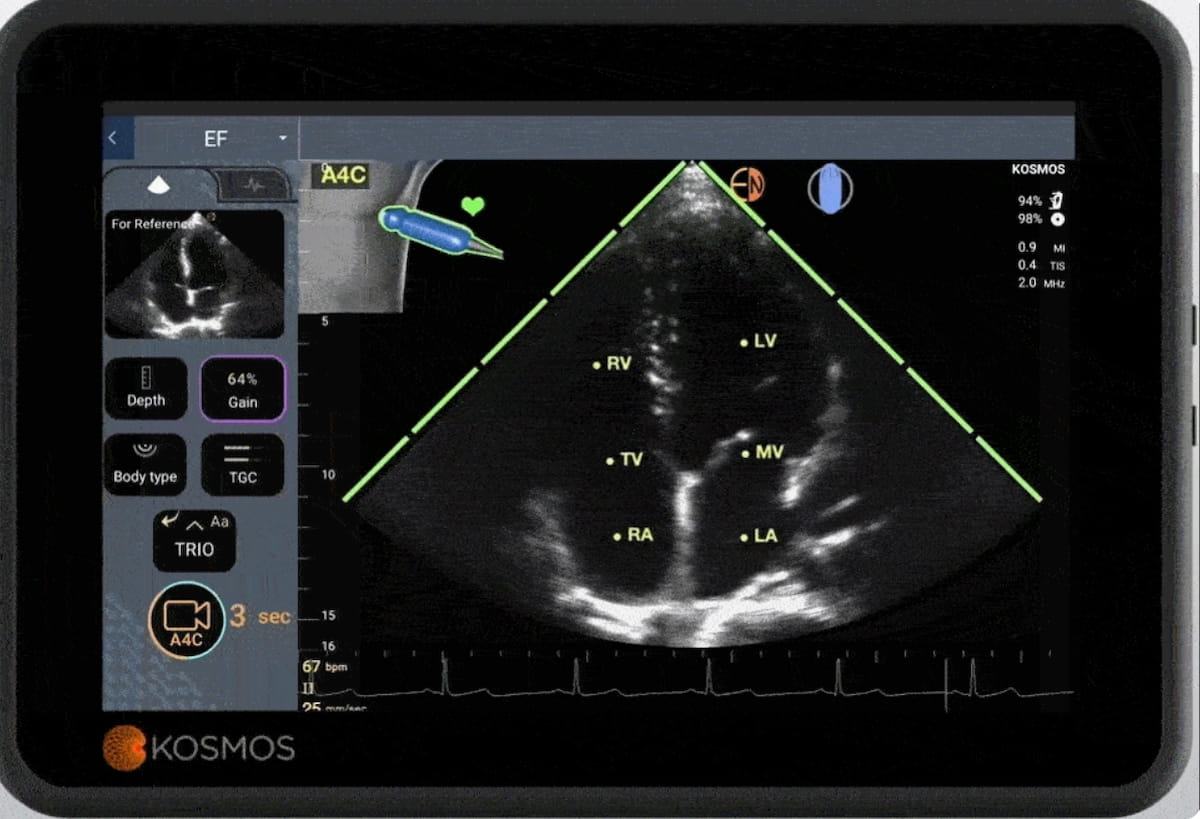

Offering enhanced utility for assessing urinary incontinence, bladder emptying and urinary retention, the Clarius Bladder AI ultrasound software reportedly provides bladder volume measurement in seconds.